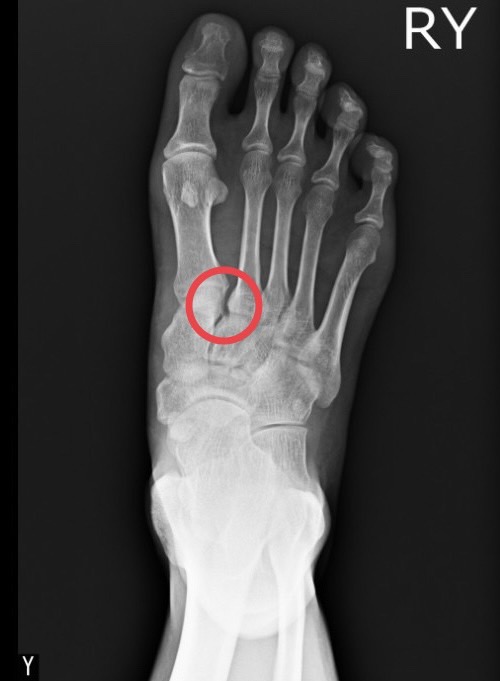

30歲小豪在參加馬拉松比賽時踩空跌倒造成右腳掌疼痛腫脹,腳底也出現瘀血。第一時間至附近醫院的急診室檢查時沒有看到骨折,醫師給了止痛藥並囑咐要抬高冰敷、好好休息。然而,3個禮拜了腳掌依舊瘀青腫脹,一踩就痛。來到大里仁愛醫院骨科的運動醫學特別門診,才發現是腳掌的蹠跗關節韌帶受傷。在劉永川醫師安排微創鋼釘固定手術治療及6週的石膏保護,現在終於回到日常生活,健步如飛。

大里仁愛醫院骨科部長黃贊文醫師表示,很多民眾也許記憶猶新,2008年當時在紐約洋基棒球隊的台灣之光王建民在奮力跑壘時受傷,當時就是發生右腳掌的蹠跗關節韌帶拉傷,當時引起全國球迷的熱議。蹠跗關節是足弓穩定非常重要的關節,像是拱橋上最重要的基石,有許多韌帶附著在上面。蹠跗關節韌帶拉傷常發生在高能量的外傷或運動傷害。若X光上看到蹠跗關節有變寬或排列不整齊變形的狀況,最好儘早手術復位,以免影響日後足部的功能。

大里仁愛醫院運動醫學中心劉永川醫師指出,蹠跗關節受傷一般發生在中年男性比較多,會有嚴重的疼痛並且無法負重站立。診斷主要藉由X光或進一步電腦斷層的檢查,核磁共振則可以進一步用在鑑別韌帶的受傷。若是蹠跗關節移位嚴重或合併複雜的骨折需要較大傷口並使用鋼板及骨釘來復位及固定;若是像小豪一樣僅是蹠跗關節韌帶受損則可使用微創骨釘的方式來治療。